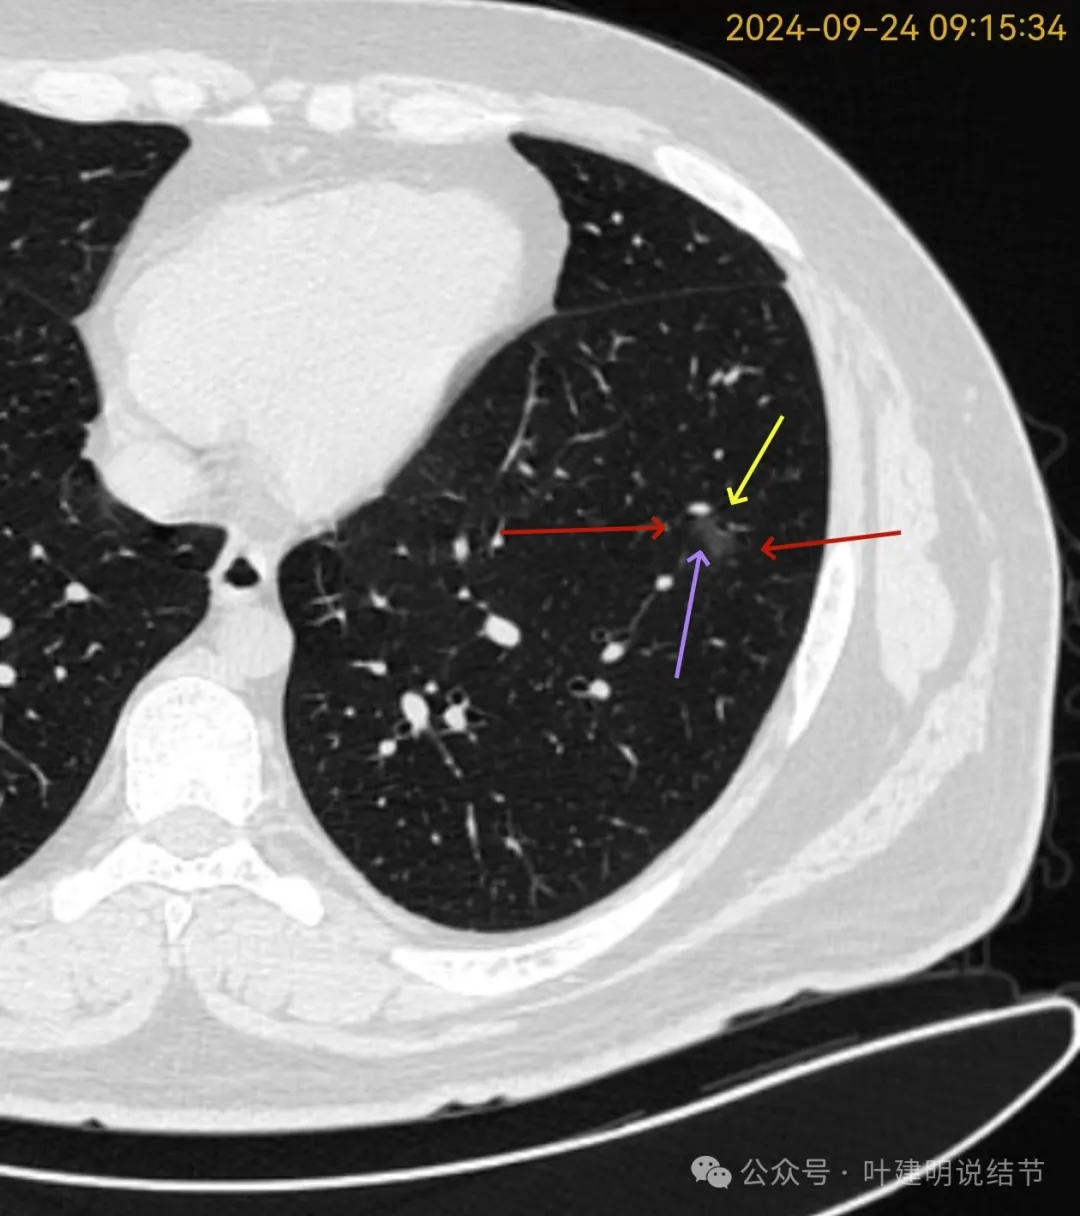

再看2024年9月复查的片子:

病灶出现,磨玻璃密度。有微小血管与细支气管通气征。

邻近细支气管扩张、边缘细毛刺、整体轮廓清。

有毛刺征,整体轮廓清,与血管之间间隙消失。

毛刺、血管征、邻近支气管扩张、整体轮廓清,病灶与血管间隙消失。

有少许偏实性成分,整体轮廓清。

纯磨密度,不太纯,血管贴边,血管与病灶间隙消失,整体轮廓与瘤肺边界清。

血管弯征可见、细毛刺明显、细支气管扩张,血管进入。

密度总体不高,轮廓与边界清楚。

密度较淡,轮廓较清。

边缘区密度淡且较纯,轮廓清楚。